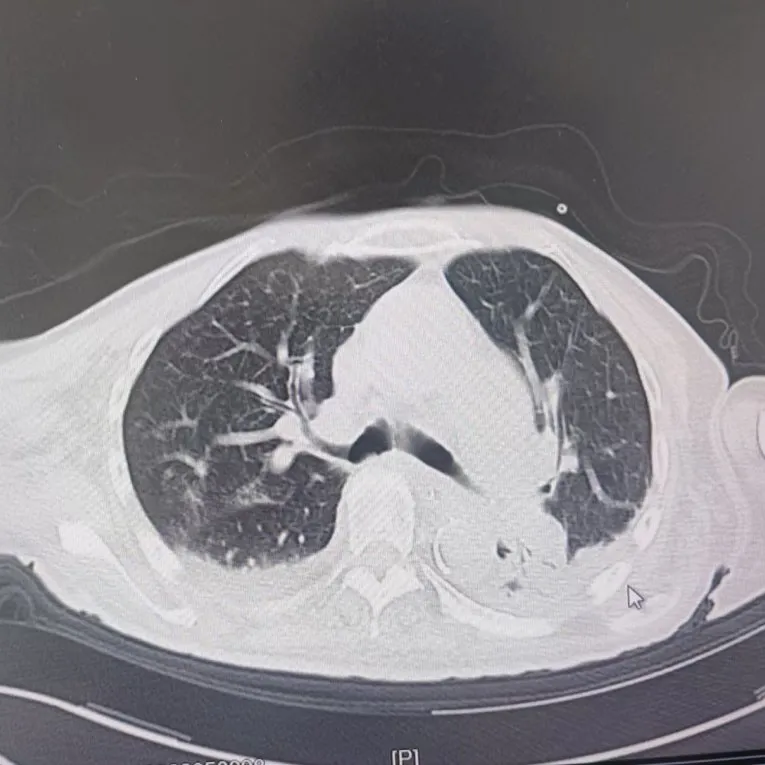

引言 / / Introduction 年近8旬的陈阿姨(化名)因脑梗长期瘫痪在床,康复期间突然高烧不退,体温升至39℃,在抗感染过程中,她并发高渗性脱水,病情急剧恶化,被紧急送入ICU。此时,她已气管切开,依靠呼吸机维持呼吸,并伴有低蛋白血症、低钾高钠血症及房颤等多种危重情况,命悬一线! PART. 01 多重泛耐药菌叠加大量基础病 治疗陷入“死胡同” 呼吸与危重症医学科及ICU通力协作,稳住患者生命体征。治疗过程中,进一步的病原学检查结果令人心惊:陈阿姨的肺部遭遇多种“超级细菌”混合侵袭,包括铜绿假单胞菌、鲍曼不动杆菌、嗜麦芽窄食单胞菌、金黄色葡萄球菌、木糖氧化无色杆菌、粘质沙雷菌等高度耐药菌,堪称耐药菌“大本营”。这些细菌对常用抗生素几乎全部耐药,治疗难度高,死亡率高。 治疗前患者肺部影像 PART. 02 多学科强强联手 量身定制攻坚方案 面对无药可用的困境,呼吸科没有放弃!宋刚主任带领团队联合药学部、检验科、重症医学科成立多学科治疗组,根据患者身体情况实时调整用药,逐一攻破耐药菌。这场与“超级细菌”的拉锯战持续了30多个日夜。 在医护日夜坚守和家属全力配合下,陈阿姨的感染终于被遏制:高烧退了,肺部阴影消散了!就在即将宣告胜利时,又发现她存在泌尿感染问题,随即转入泌尿外科协同治疗。当宋主任回访时,看到陈阿姨精神焕发、体温平稳,所有参与救治的人都感慨万分!这场救治,正是呼吸与危重症医学科攻坚耐药菌硬实力的生动体现! 治疗后患者肺部影像 从“无药可用”到“绝处逢生”,此次成功救治,集中体现了呼吸与危重症医学科以耐药菌精准诊治为核心的学科特色与技术优势。面对一次次的严峻挑战,科室始终秉持“生命至上、知难而进”的信念,以多学科协作为平台,凭借个体化精准用药策略,为患者寻找生机,为更多陷入困境的患者和家庭带去了实实在在的希望。 PART. 03 人民医院 人民名医 宋刚 主任医师 ·葫芦岛市第二人民医院呼吸与危重症医学科主任 ·辽宁省生命科学学会东北呼吸与危重症医学(PCCM)分会辽宁省基层委员会副主任委员 ·辽宁省细胞生物学学会放射粒子治疗专业委员会理事 ·辽宁省抗击新冠肺炎疫情先进个人 ·葫芦岛市劳动鉴定委员会专家库成员 ·葫芦岛市医学会呼吸内科学分会第三届委员会副主任委员 专业特色:擅长呼吸系统疑难及急危重患者的救治,如急慢性支气管炎、支气管哮喘、慢性阻塞性肺疾病、肺炎、肺栓塞、肺癌、间质性肺疾病、睡眠呼吸暂停综合征等,尤其擅长有创无创机械通气、支气管镜下相关检查及治疗(TBNA、气道支架置入术、球囊扩张等)、全肺灌洗术等领先技术,发表国家级期刊多篇。